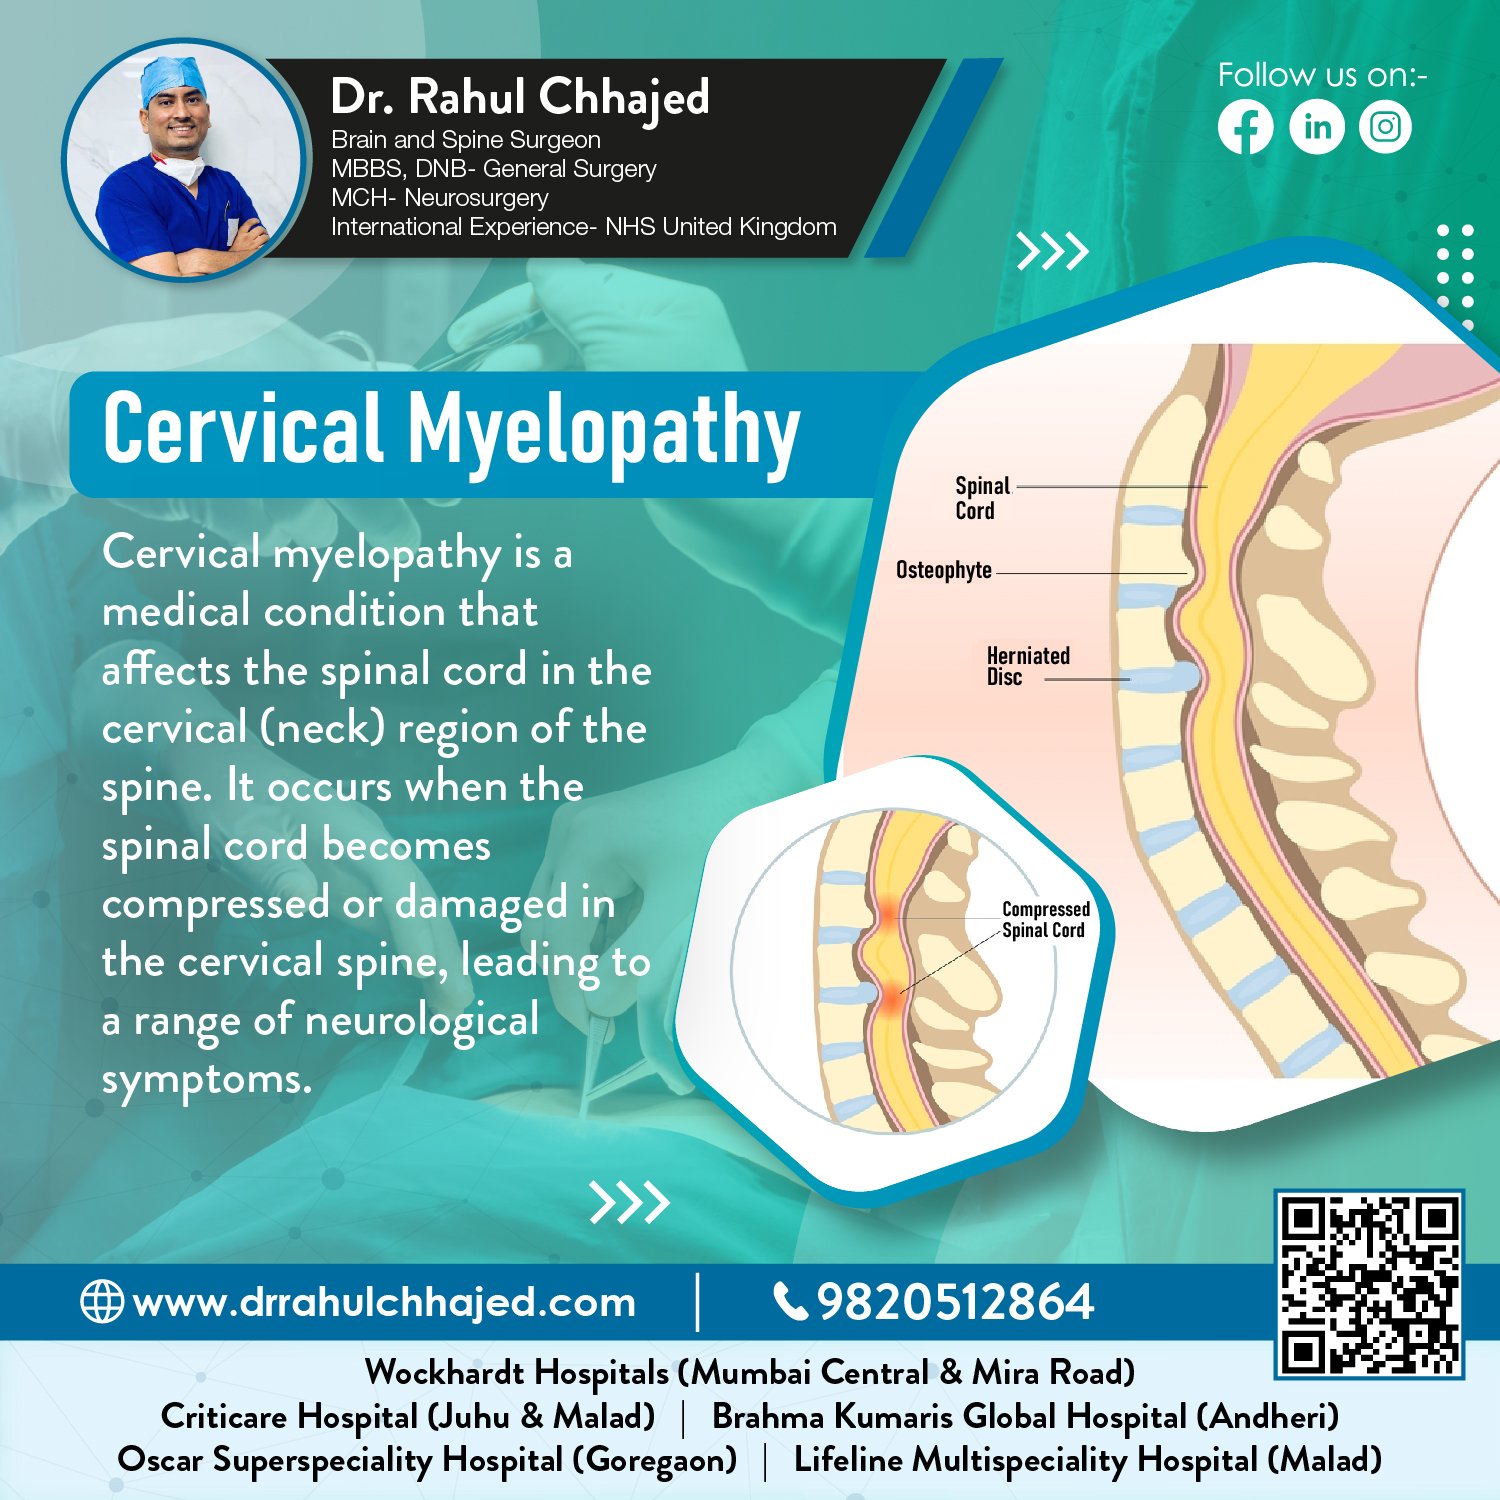

Spine Surgery

Dr. Rahul is a highly experienced spine surgeon specializing in diagnosing and treating spinal conditions. He performs a wide range of surgical options for spinal conditions, including minimally invasive techniques, spinal fusion, and disc replacement.

Minimal invasive spine surgery / endoscopic spine surgery

Endoscopic spine surgery offers many benefits over traditional open surgery, including smaller incisions, less blood loss, and faster recovery times. Dr. Rahul is the go-to specialist for endoscopic spine surgery in the area.